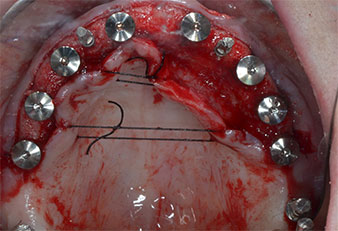

Tres años después, llegó el momento de colocar una prótesis del mismo tipo en el maxilar superior. Basándose en una planificación mediante tomografía computarizada de haz cónico (CBCT, por sus siglas en inglés), se evitó la necesidad de realizar una elevación del seno utilizando implantes cortos, mientras que una plantilla quirúrgica sirvió para transferir las posiciones planificadas al borde alveolar (figuras 1 y 2).

Para marcar las posiciones del implante y realizar la preparación piloto, se utilizó un inserto piezoeléctrico (Piezomed I1) con revestimiento de diamante y forma de llama (figura 3). Se tomaron precauciones para realizar movimientos hacia arriba y hacia abajo, con una potencia reducida, una irrigación completa y una baja presión (por debajo de 300 g). A continuación, se aplicó un inserto piloto (Piezomed I2A/I2P) para aumentar el diámetro inicial de 2 mm de los sitios de implante (figura 4), seguido de un inserto de 3 mm (Fig. 5).

Debido al hueso relativamente duro (D2) existente en el sector anterior, los sitios de los implantes largos de 10 mm de las posiciones 11 y 21 se finalizaron con una fresa rotatoria de 4 mm de diámetro, en combinación con un contra-ángulo quirúrgico WS-75 L de W&H, el motor de implantes Implantmed de W&H y el módulo opcional Osstell ISQ de W&H. En cambio, debido a la existencia de hueso blando, los sitios posteriores se prepararon hasta un diámetro final de 3 mm utilizando el inserto Piezomed I3P. Por último, los implantes se colocaron a nivel crestal para su osteointegración durante tres meses (figuras 6-10). La prótesis existente se mantuvo sobre cuatro implantes provisionales (figura 8).